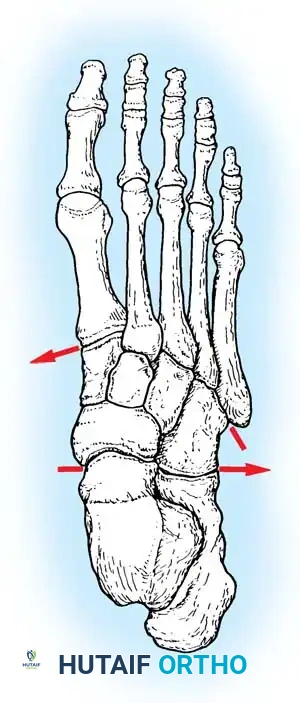

Fig. 86-37 Dorsal view of foot showing contour of tarsometatarsal joints.

Fig. 86-37: Dorsal view of the foot illustrating the recessed contour of the tarsometatarsal joints, highlighting the keystone base of the second metatarsal.

Notably, there is no transverse ligament connecting the bases of the first and second metatarsals. Stability here relies entirely on the Lisfranc ligament, a stout interosseous ligament running from the lateral aspect of the medial cuneiform to the medial base of the second metatarsal.

Critical Radiographic Parameters:

1. AP View: The medial shaft of the 2nd metatarsal must align perfectly with the medial aspect of the middle cuneiform.

2. Oblique View: The medial shaft of the 4th metatarsal must align perfectly with the medial aspect of the cuboid.

3. Lateral View: The dorsal cortices of the metatarsals should be flush with the cuneiforms (no dorsal subluxation).

4. The "Fleck Sign": A small bony avulsion fragment in the space between the medial cuneiform and the 2nd metatarsal base represents an avulsion of the Lisfranc ligament and indicates gross instability.